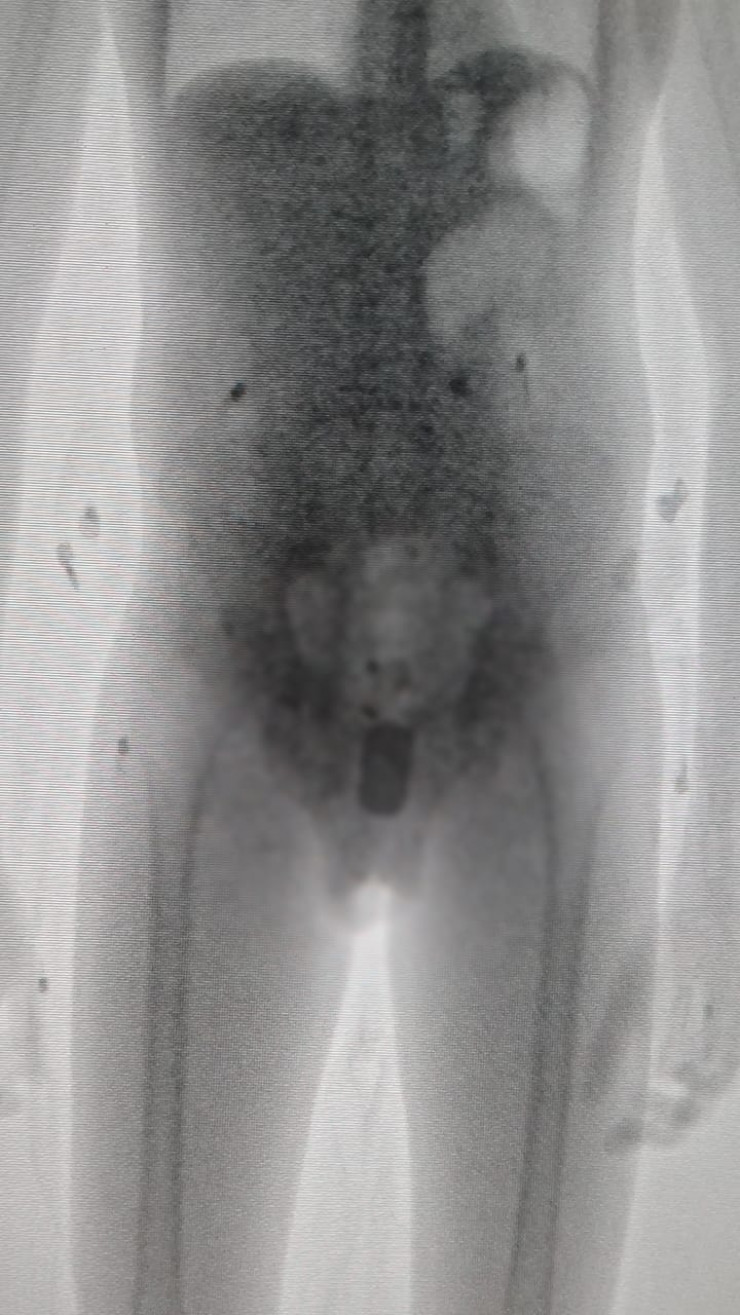

Сотовый телефон обнаружили в кишечнике заключенного в Акмолинской колонии, передает Tengrinews.kz со ссылкой на пресс-службу ДУИС по Акмолинской области.

Как сообщили в департаменте, по прибытии в учреждение ЕЦ-166/18 акмолинского ДУИС, 36-летний гражданин из Жамбылской области, осужденный за преступные действия в отношении представителя власти, после предложения сотрудниками группы досмотра пройти через рентген оборудование рассказал, что при нем имеется запрещенный предмет, правда, предъявить он его не может, поскольку хранится гаджет в кишечнике.

"Рентгеновский снимок показал, что, кроме телефона Nokia размером 6 сантиметров, там же была и действующая сим-карта", - сообщили в пресс-службе.